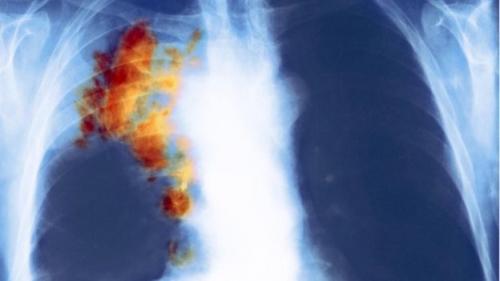

صورة أشعة توضح سرطان في الرئة اليمنى